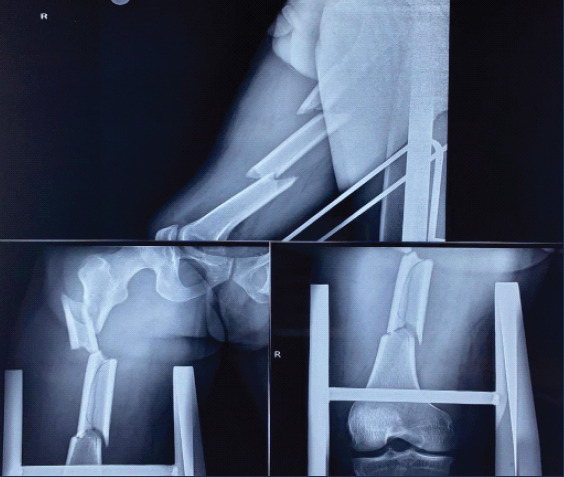

Case report: A 35-year-old man with multiple-level femoral fractures at the subtrochanteric, diaphyseal, and supracondylar femoral regions - a condition known as double-SFFs - presented to our emergency department due motor vehicle collision. Intramedullary nailing was done without the use of a fracture table for fixation, and because there was a completely separated femoral fragment between the fracture lines, fracture reduction was difficult during reaming due rotation of the middle fragment.